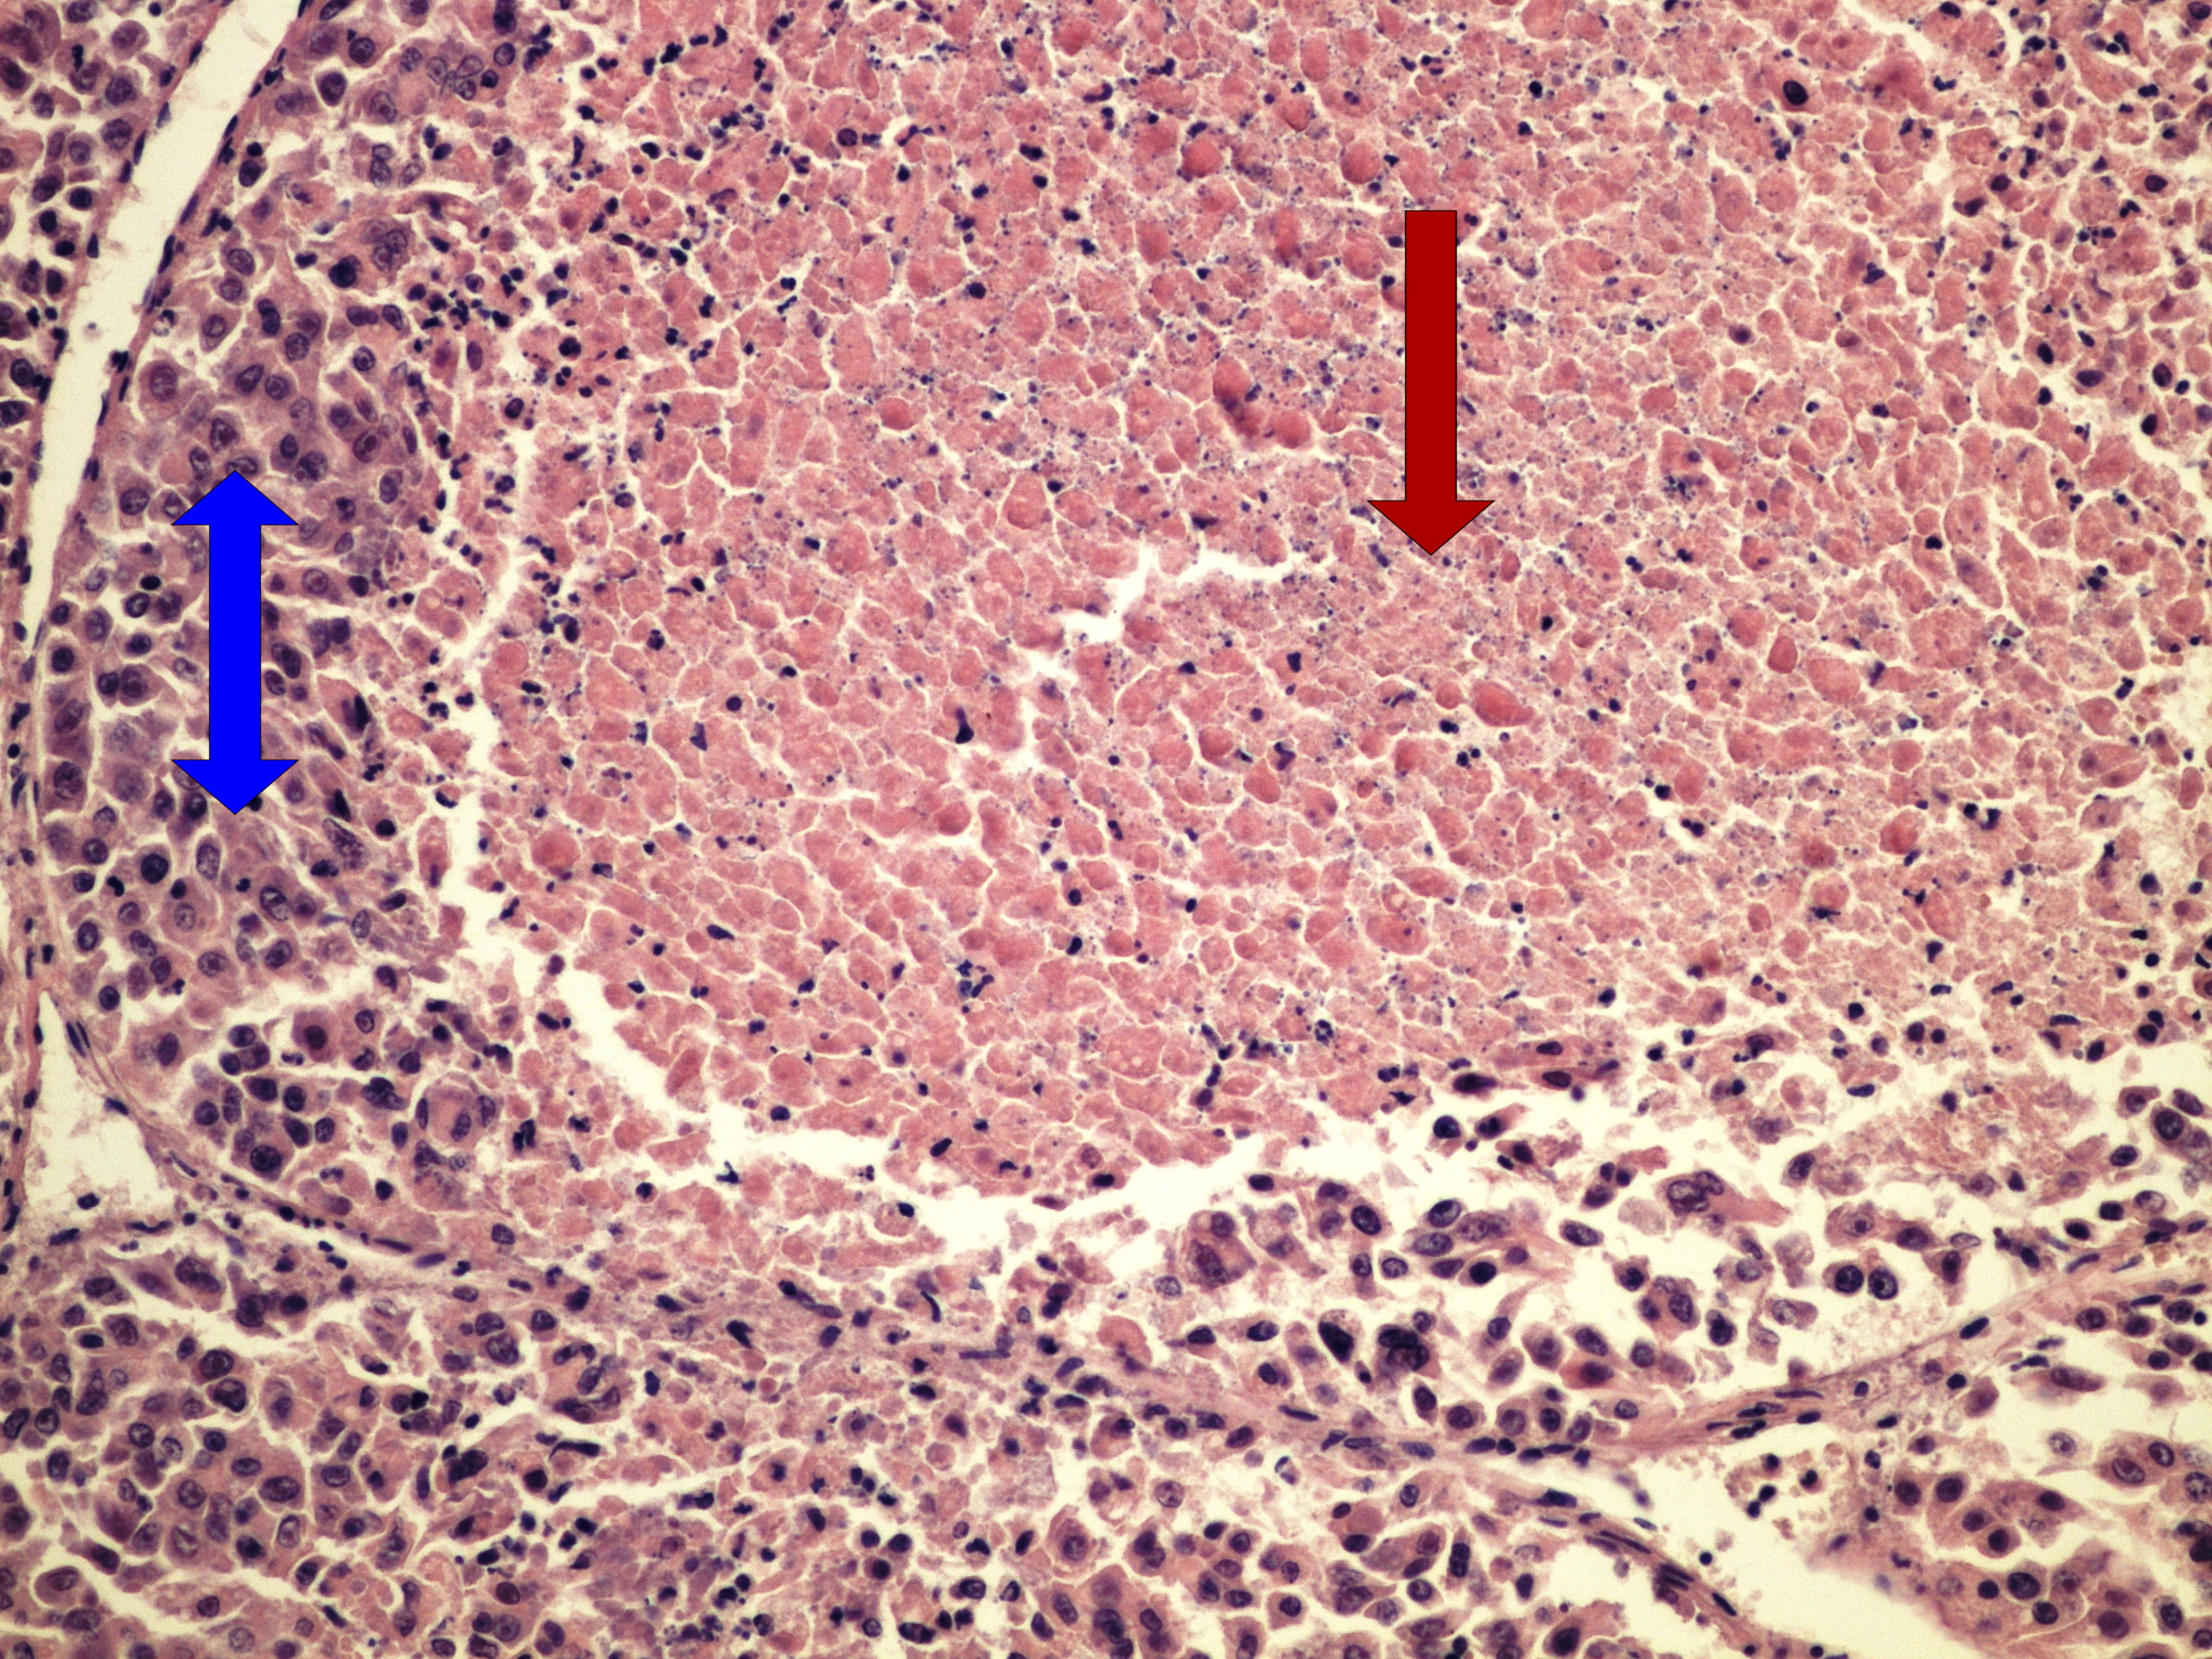

Preparát č.13 a č.14 - hepatocelulární karcinom

Struktury

- nekróza

- tumor

- nádorový trámec